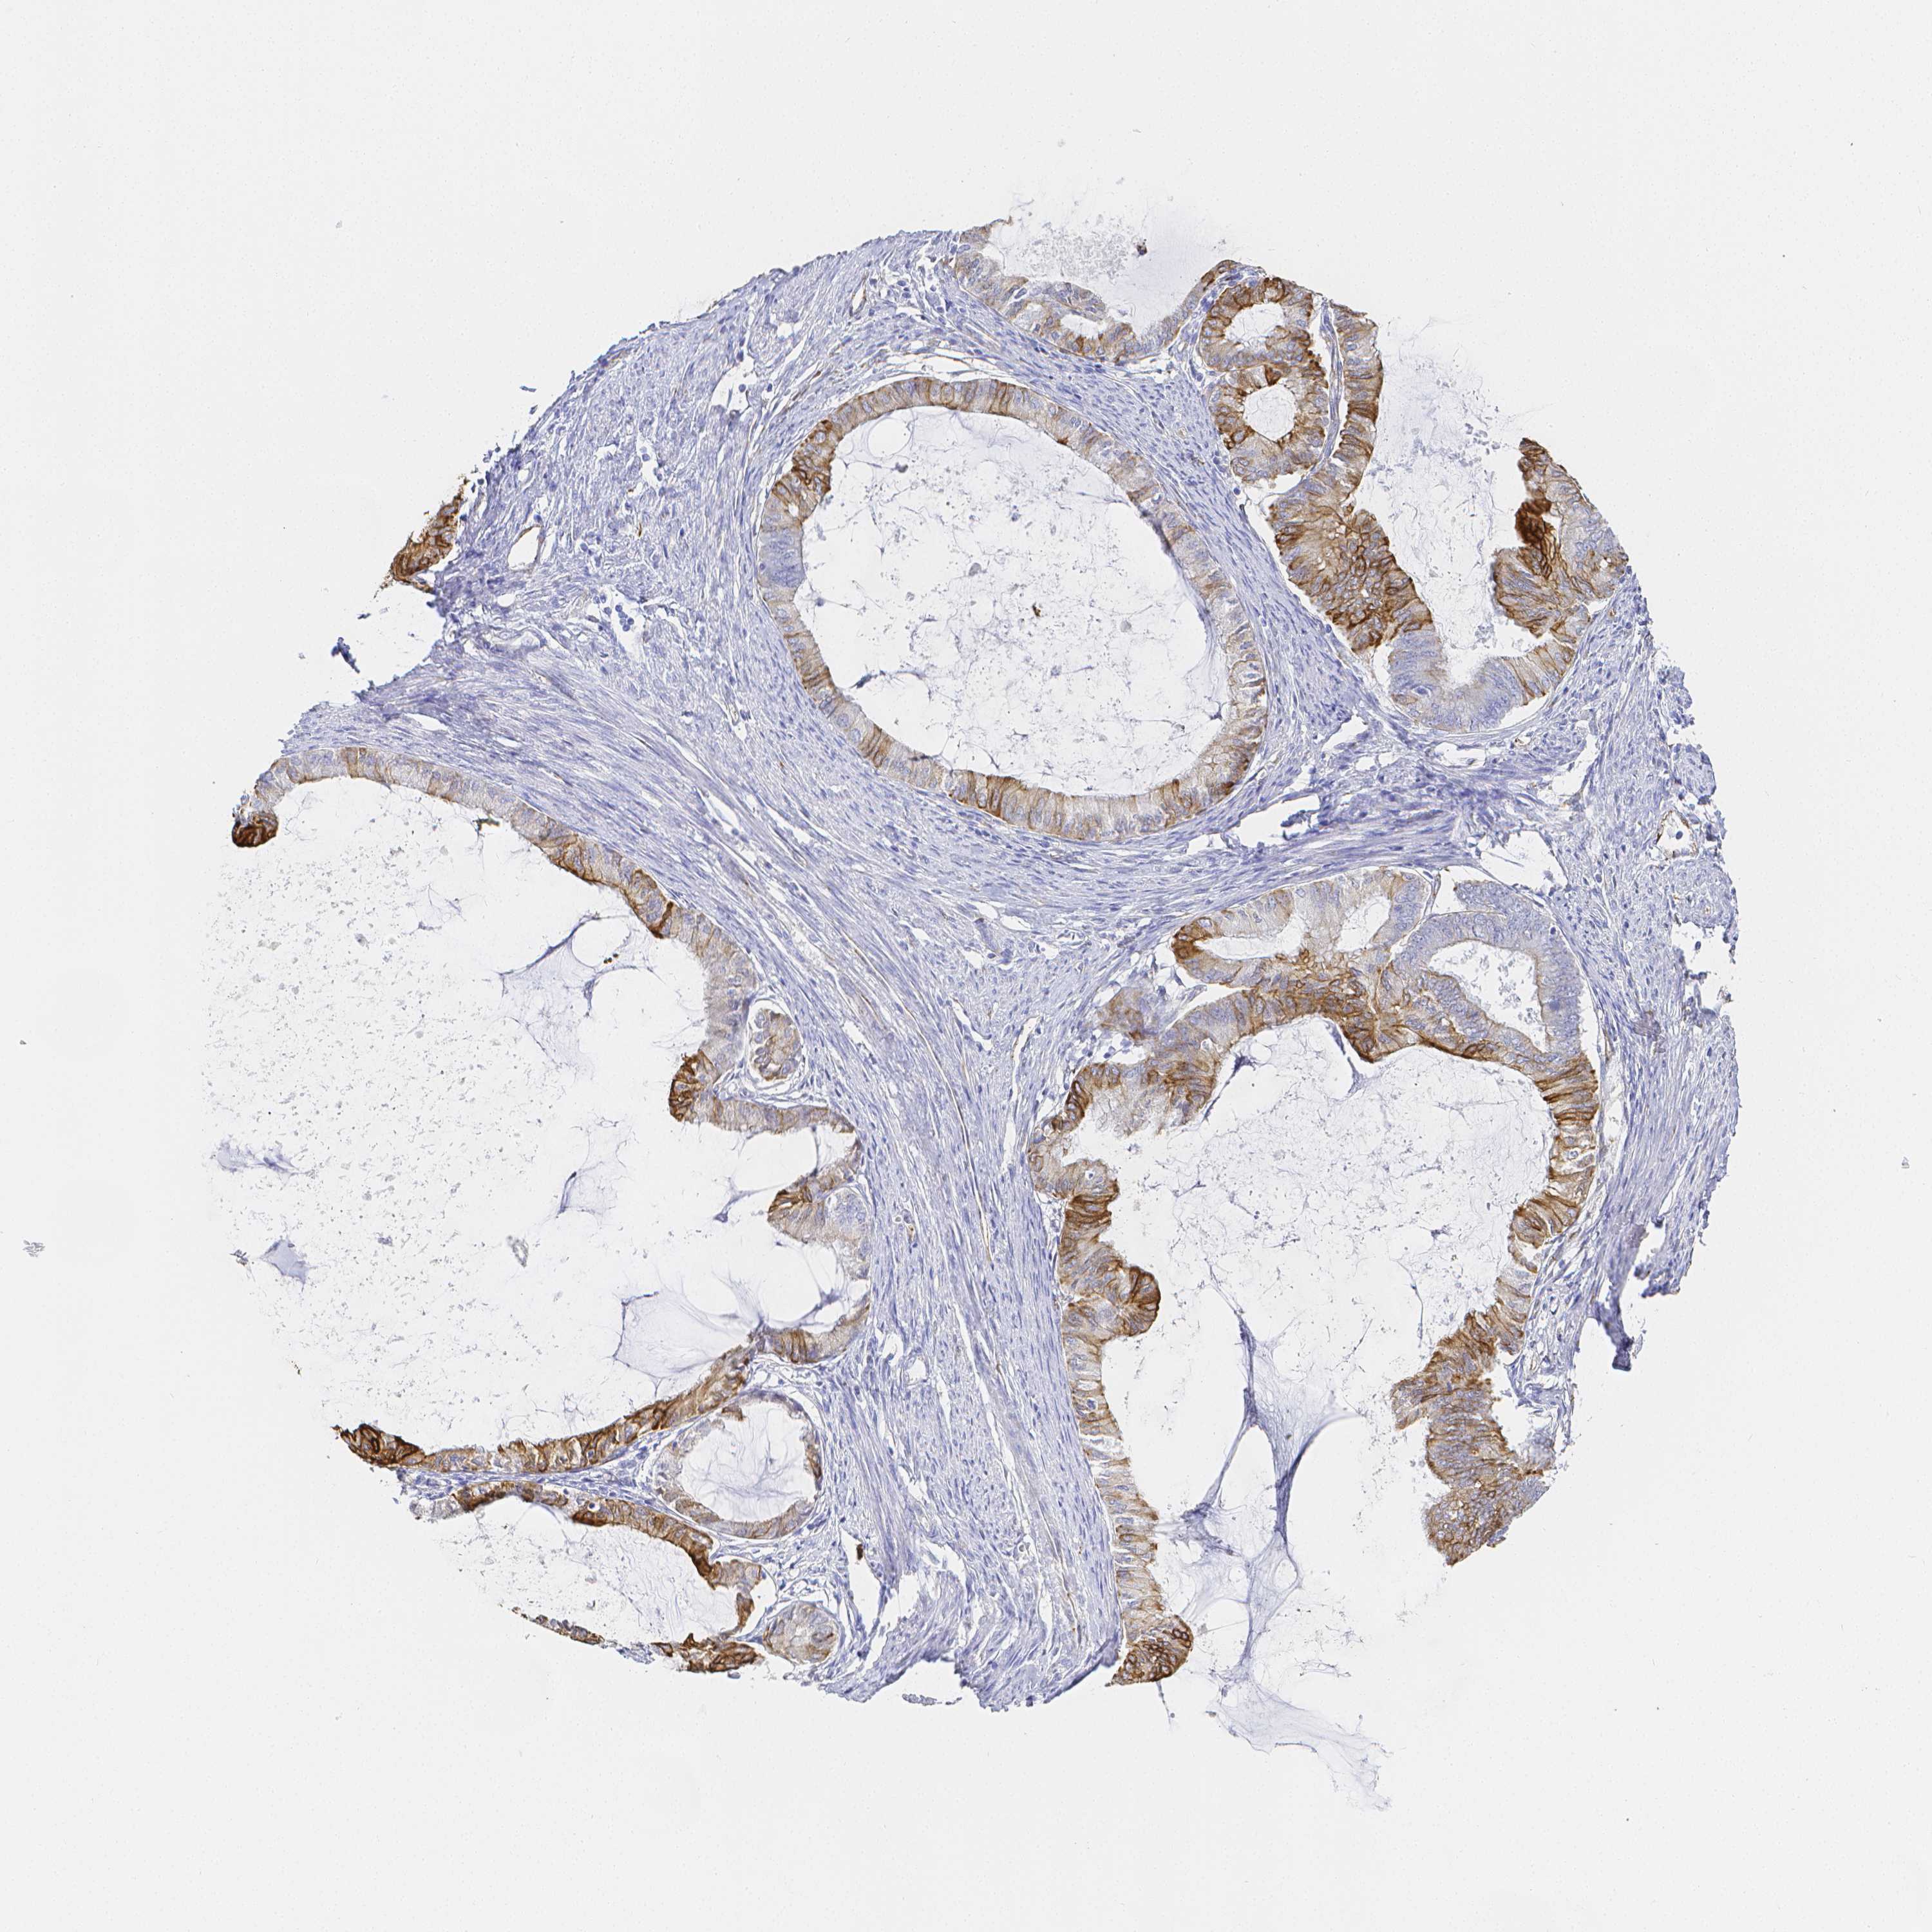

ENDOMETRIAL CANCER - Protein expressioni

A mouse-over function shows sample information and annotation data. Click on an image to view it in a full screen mode. Samples can be filtered based on level of antibody staining by selecting one or several of the following categories: high, medium, low and not detected. The assay and annotation is described here.

Note that samples used for immunohistochemistry by the Human Protein Atlas do not correspond to samples in the TCGA dataset.

Antibody stainingi

Antibody staining in the annotated cell types in the current human tissue is reported as not detected, low, medium, or high, based on conventional immunohistochemistry profiling in selected tissues. This score is based on the combination of the staining intensity and fraction of stained cells.

Each image is clickable and will lead to virtual microscopy that enables deeper exploration of all samples and also displays staining intensity scores, fraction scores and subcellular localization as well as patient and tissue information for each sample.

Antibody HPA055245

Staining

High

Medium

Low

Not detected

Intensity

Strong

Moderate

Weak

Negative

Quantity

>75%

75%-25%

<25%

None

Location

Nuclear

Cytoplasmic/membranous

Cytoplasmic/membranous,nuclear

Adenocarcinoma, NOS

Adenocarcinoma, metastatic, NOS